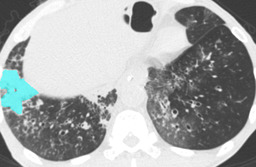

In this paper, we define partial annotation as an annotation format in which only one class is chosen for the annotation and only pixels belonging to the chosen class are annotated per image. For example, in Figure 1(a), although there is ground glass opacity in the image, only consolidation is chosen for annotation and pixels of consolidation are annotated. Partially annotated dataset is less informative for training, however, it is much easier to create compared to fully annotated dataset since annotators only need to focus on one class at a time during the annotation task.

Partially annotated datasets have been utilized previously [8, 9]. In this paper, we propose a new weak supervision technique that fully utilizes partially annotated dataset. Throughout this paper, each DLD pattern is represented or painted in the following colors (CON:cyan, GGO:yellow, HCM:red, EMP:green, NOR:brown.)

Statistics of our dataset are shown in Table 1 and typical images and their annotations for each DLD pattern are shown in Figure 1. In our partially annotated dataset, all the pixels in a slice were manually classified into two classes: dominating DLD pattern and other tissues. In other words, all the pixels in our dataset were assigned one of the labels from either of the two label sets, Lstrong={lCON,lGGO,lHCM,lEMP,lNOR}subscript𝐿𝑠𝑡𝑟𝑜𝑛𝑔subscript𝑙𝐶𝑂𝑁subscript𝑙𝐺𝐺𝑂subscript𝑙𝐻𝐶𝑀subscript𝑙𝐸𝑀𝑃subscript𝑙𝑁𝑂𝑅L_{strong}=\{l_{CON},l_{GGO},l_{HCM},l_{EMP},l_{NOR}\} or Lweak={lCON¯,lGGO¯,lHCM¯,lEMP¯,lNOR¯}subscript𝐿𝑤𝑒𝑎𝑘subscript𝑙¯𝐶𝑂𝑁subscript𝑙¯𝐺𝐺𝑂subscript𝑙¯𝐻𝐶𝑀subscript𝑙¯𝐸𝑀𝑃subscript𝑙¯𝑁𝑂𝑅L_{weak}=\{l_{\overline{CON}},l_{\overline{GGO}},l_{\overline{HCM}},l_{\overline{EMP}},l_{\overline{NOR}}\}. For example, in Figure 1(a), colored pixels were labeled as lCONsubscript𝑙𝐶𝑂𝑁l_{CON} and all the other pixels were labeled as lCON¯subscript𝑙¯𝐶𝑂𝑁l_{\overline{CON}}. In this paper, we call pixels of label lLweak𝑙subscript𝐿𝑤𝑒𝑎𝑘l\in L_{weak} and lLstrong𝑙subscript𝐿𝑠𝑡𝑟𝑜𝑛𝑔l\in L_{strong} as weakly annotated pixels and strongly annotated pixels respectively. Our pixel-wise annotations were created in the following steps. First, up to 3 slices were chosen for the annotation for each HRCT scan and for each slice, one representing DLD pattern was chosen by a radiologist. Second, three radiologists performed pixel-wise binary annotation (e.g. binary annotation between lCONsubscript𝑙𝐶𝑂𝑁l_{CON} or lCON¯subscript𝑙¯𝐶𝑂𝑁l_{\overline{CON}}) for each slice. Finally, the radiologists’ annotations were merged by taking majority classes for each pixel (i.e. pixels labeled as a DLD pattern by more than 2 radiologists became the corresponding DLD pixel). In addition to the DLDs annotation, lung fields were manually segmented under the supervision of radiologists and training and testing were conducted only within the lung fields.

Figure 1: Typical slices for each DLD classes. Slices of HRCT are shown in lung window setting (window-center=-600, window-width=1500) with annotated labels superimposed in transparent colors. Note that even if more than one DLD patterns existed, only one DLD pattern was chosen and annotated for a slice to facilitate the annotation process.